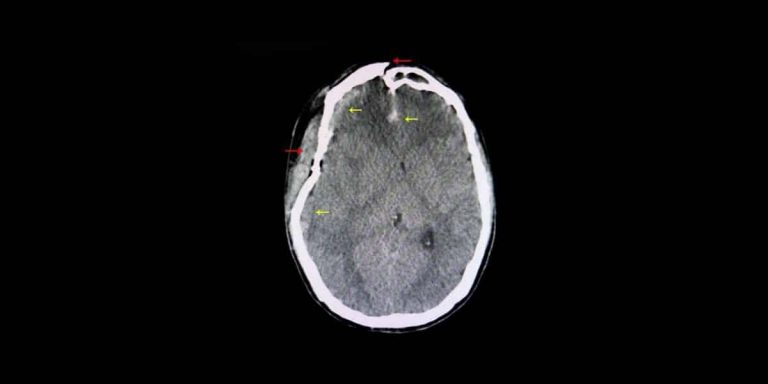

When Can a Car Accident Cause Brain Damage?

Head injuries are extremely common after motor vehicle accidents. One of the many problems with a head injury is that the person suffering from it